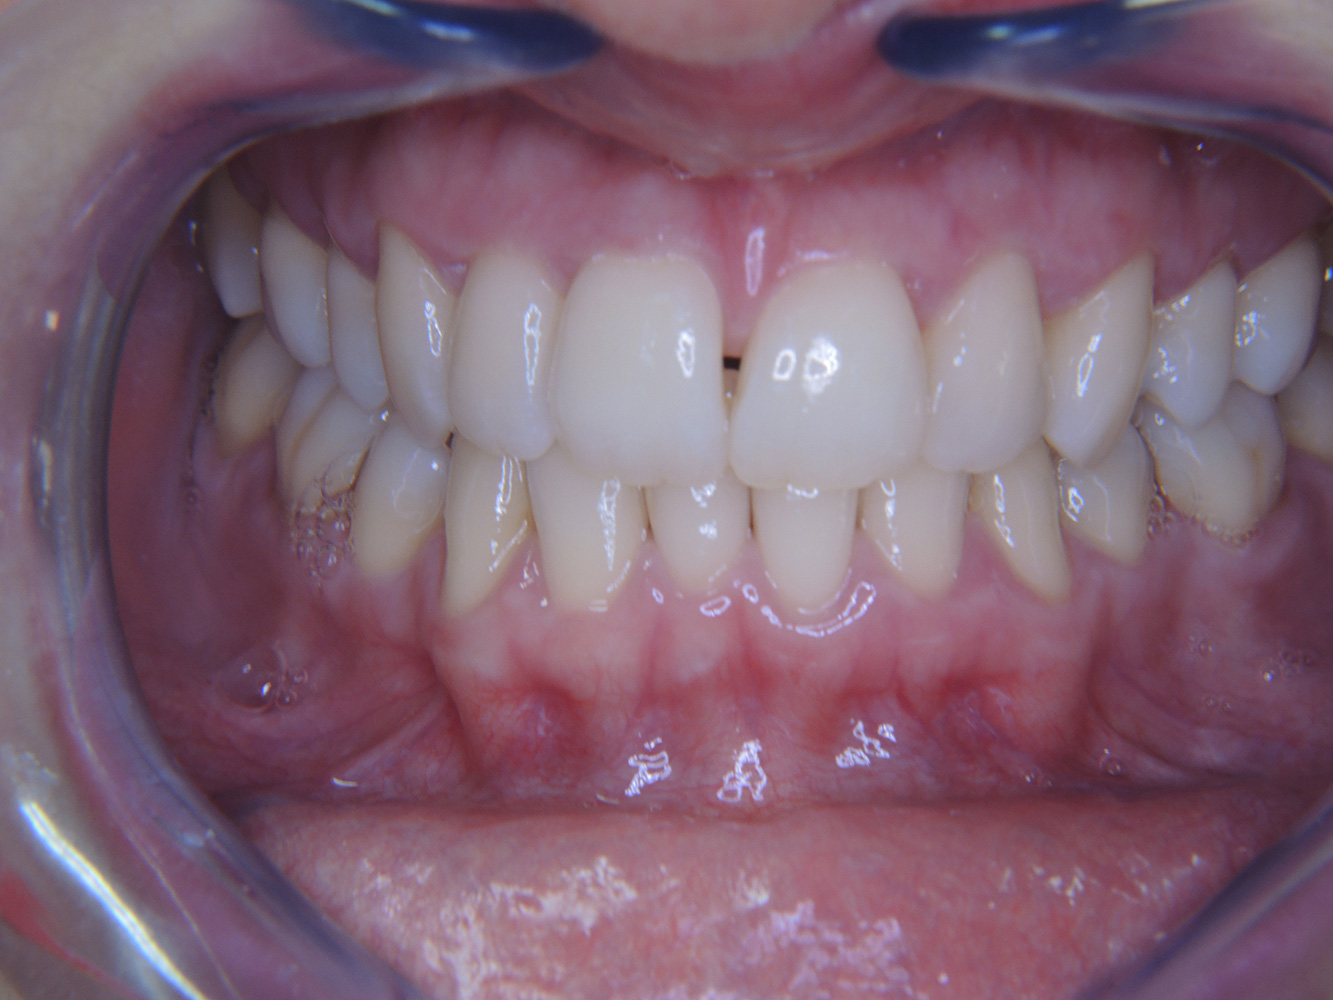

The 68-year-old patient has no general health conditions and is not taking any medication that may be relevant to her oral health, and her lifestyle does not pose any particular risk. The patient has two dental implants (3rd quadrant, for five years) and a previous case of periodontal disease (stage IV, grade B periodontitis) with tooth loss. Currently the periodontal conditions are stable. However, periodontitis significantly increases the biological complications of implantations and there is a risk of implant loss (21). Four recommendations can be determined for the prophylaxis session. more